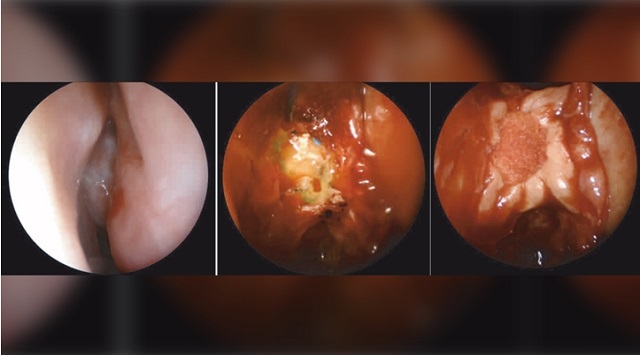

JAMA Otolaryngology/University of Iowa Hospitals and Clinics tarafından yayınlanan bir rapora göre; burun çubuğu ile COVID-19 testi uygulanan bir kadının burnundan beyin omuriliği sıvısı akıntısı gelmiştir.

2020 yılı Ekim ayında JAMA (The Journal of the American Medical Association – Amerikan Medikal Birliği Dergisi) Otolaryngology – Head & Neck Surgery dergisinde yayınlanan bir rapora göre; burun çubuğu testi esnasında beyin zarı delinen bir kadında, beyin omurilik sıvısı sızıntısı görülmüştür. Birleşik Devletler’de başka bir kadında da geçtiğimiz günlerde benzer bir vakaya rastlanmıştır. Burun çubuğu kullanımını değerlendiren ve görüşlerini JAMA Otolaryngology – Head & Neck Surgery dergisinde paylaşan araştırmacılar, özellikle uygun kullanılmayan burun çubukları nedeniyle, rutin olarak test yaptıran milyonlarca insanın risk altında olduğu uyarısında bulunmuşlardır.

Doktorlar kadının burnu içinde bir kitle tespit etmişlerdir ve bu kitlenin burun çubuğu uygulaması esnasında oluşarak beyin omurilik sıvısının akıntısına neden olduğuna inanmaktadırlar. Kaynak: JAMA Otolaryngology/University of Iowa Hospitals and Clinics.